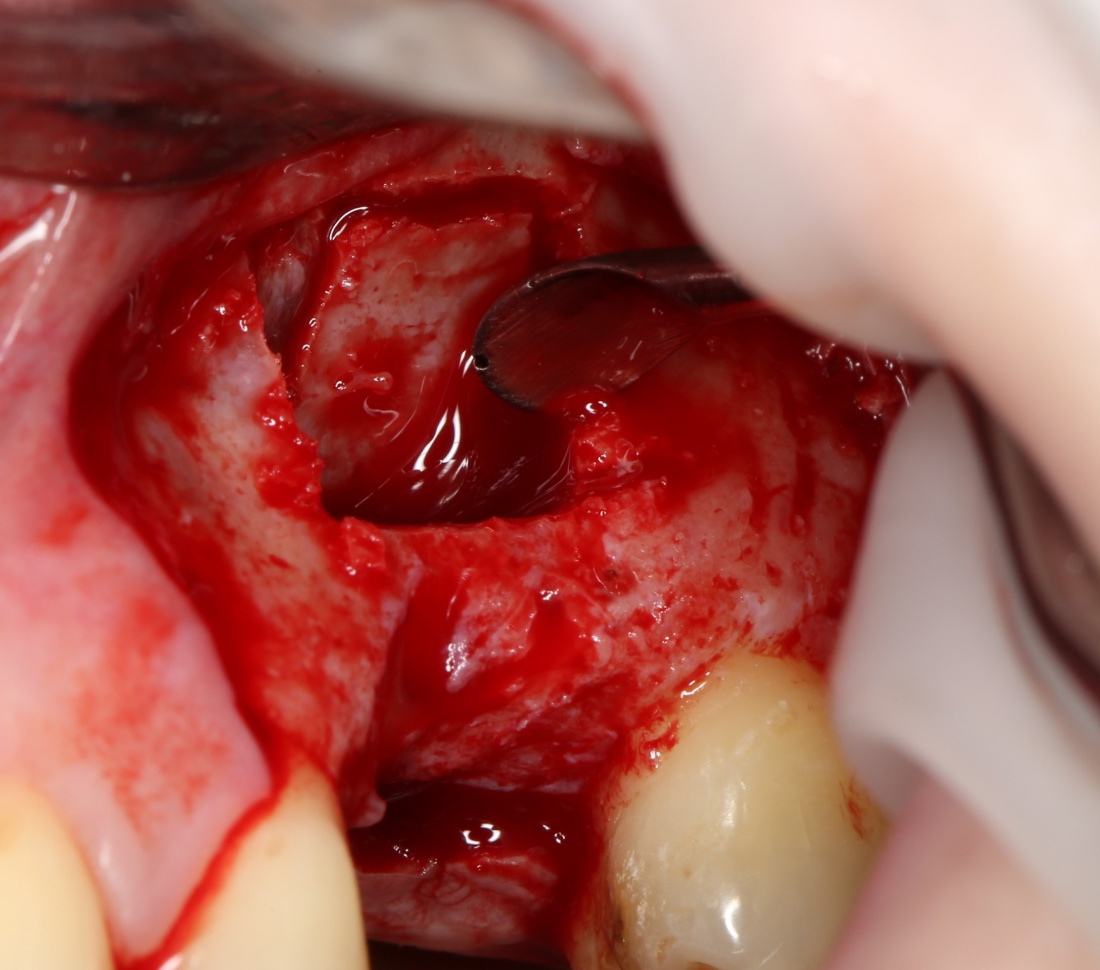

Кстати, обрати внимание на ширину альвеолярного гребня (левая картинка). Она чуть меньше 3 мм. Это объясняет, почему я засомневался в возможности установки имплантатов одновременно с остеопластикой. Понятно и без КЛКТ.

Наперво, мне нужно удалить разрушенный зуб и получить костный аутотрансплантат.

Для получения костного блока, мы открываем донорскую зону, наружную косую линию нижней челюсти.

Возвращаемся к основной операционной области. Еще раз посмотрим на альвеолярный гребень, поофигеваем от его ширины и моих грандиозных планов: